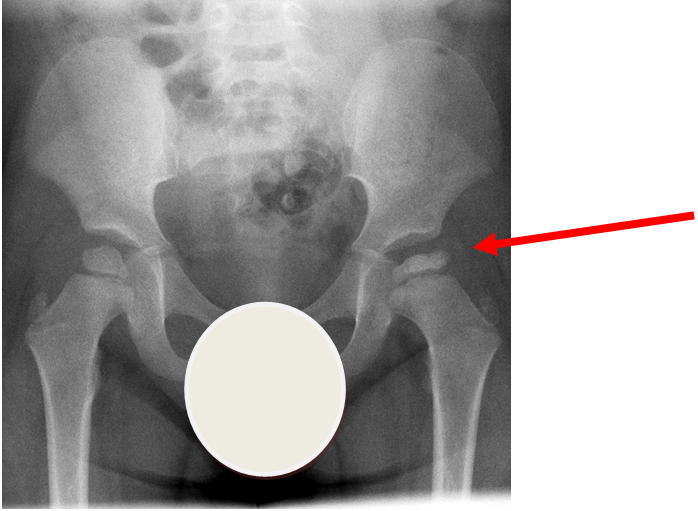

Case courtesy of A.Prof Frank Gaillard, Radiopaedia.org. From the case rID: 7980

Perthes disease or avascular necrosis of the capital femoral epiphysis is more common in boys than girls (approximately 4:1).  Onset is usually over weeks and typically between the ages of  3-9 years old.  15% are bilateral.  X-ray of the pelvis shows flattening of the femoral head with joint space widening.  X-ray changes may be absent in early disease.

The child is systemically well with no other joint involvement and no evidence of joint inflammation.

Investigation

• X-ray - AP pelvis